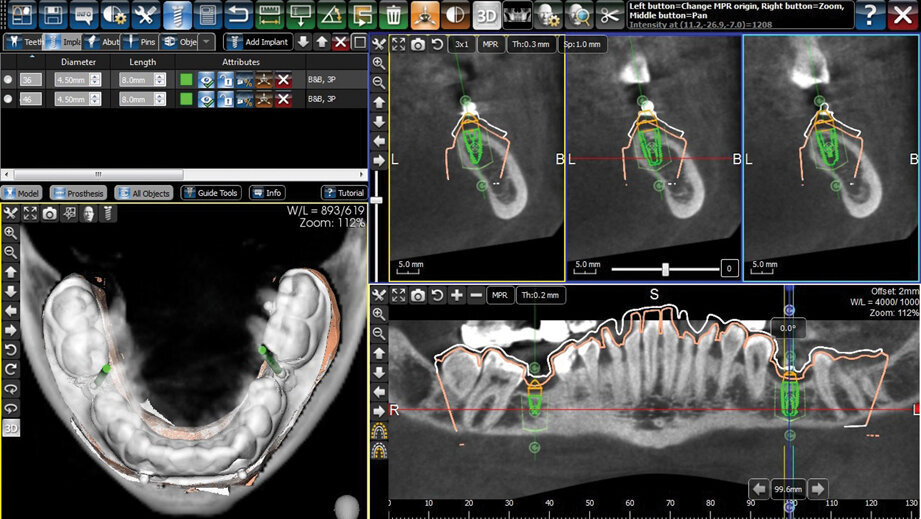

Planiranje postave implantata izvršeno je u 3Diemme 4.1 softveru (Slika 3). Pri virtuelnoj postavi implantata vodilo se računa o hirurškim smernicama kao što su udaljenost od susednih zuba I mandibularnog kanala, dokse istovremeno pazilo na angulaciju implantata I odnos sa antagonistima radi planiranja buduće protetske nadoknade. Plan je bio da se postave dva implantata B&B Duravit 3P dimenzija 4.5 x 8 mm.